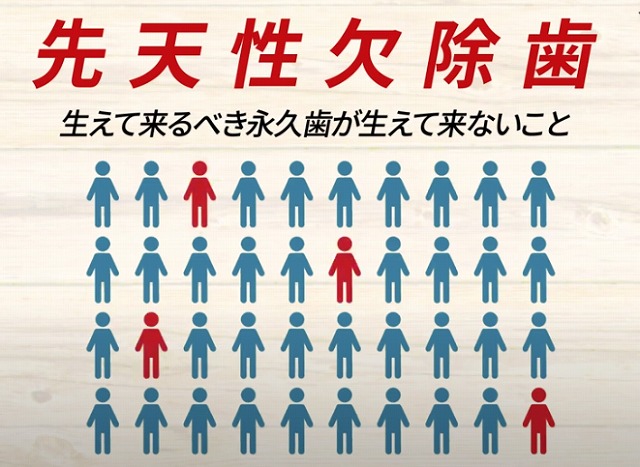

2021.08.27先天性欠除歯(生まれつき歯が生えない)は10人に1人です。

ところが現代は

増えてきています。

かつては

30人~40人に一人でしたが

最近の調べでは

10人に1人が歯が足りない

という方が増えています。